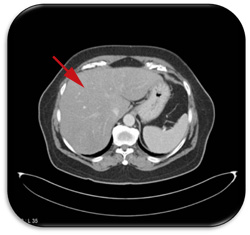

A demonstração do acúmulo de gordura geralmente é realizada através de exames complementares de imagem (ecografia, tomografia computadorizada ou ressonância nuclear magnética). Estes exames são considerados geralmente suficientes para o diagnóstico da esteatose, podendo também informar se há sinais de desenvolvimento de cirrose ou de hipertensão portal. Mas não permitem a diferenciação entre a esteatose e a esteato-hepatite nem diferenciar graus intermediários de fibrose ou de atividade da inflamação. É possível diferenciar grosseiramente o acúmulo de gordura entre leve (grau I), moderada (grau II) e severa (grau III), embora isso tenha pouca utilidade clínica.

No entanto os exames de imagem, especialmente a ultrassonografia, podem errar o diagnóstico. Doenças como a hemocromatose (onde há acúmulo de ferro no fígado) e glicogenoses (acúmulo de metabólitos de glicogênio) podem ser muito semelhantes à esteatose. Assim, considera-se que o melhor exame para o diagnóstico da esteatose é a biópsia hepática com análise histopatológica do material coletado. Além de confirmar a presença do acúmulo de gordura e diferenciar de outras doenças, permite avaliar se há hepatite e o quanto a doença está avançada em termos de fibrose.